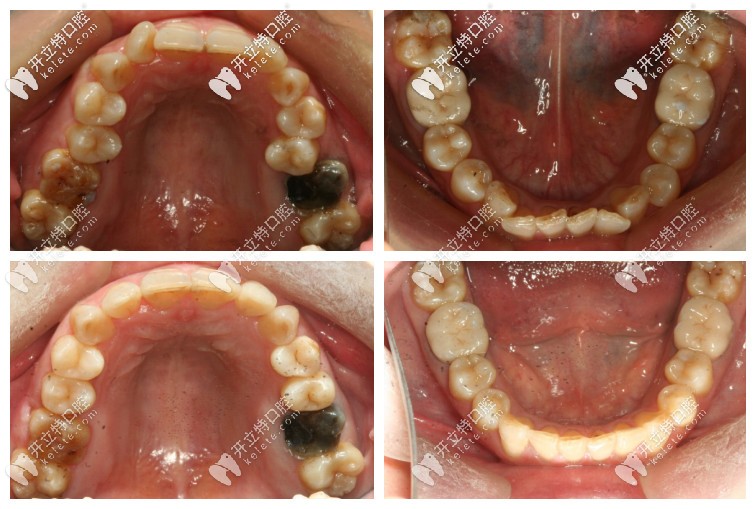

這個(gè)是矯正前后的口內(nèi)照,變化還是蠻大的,長(zhǎng)得丑,側(cè)面照就不傳了,哈哈~